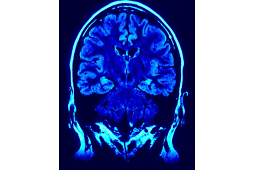

Pionierska operacja neurochirurgiczna guza mózgu

Zespół neurochirurgów Szpitala św. Rafała w Krakowie z powodzeniem przeprowadził pierwszą w województwie małopolskim i jedną z nielicznych operacji w Polsce – resekcję guza mózgu z wykorzystaniem metody śródoperacyjnego wybudzenia pacjenta.